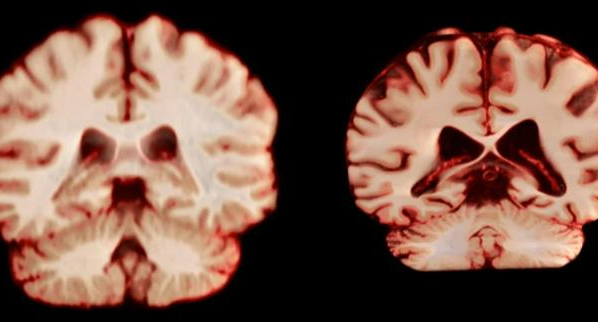

阿尔茨海默病为何“偏爱”女性?